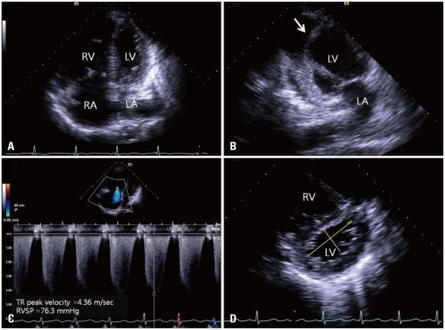

Investigations available to determine the cause of cor pulmonale include the following:[1]

• Chest x-ray – right ventricular hypertrophy, right atrial dilatation, prominent pulmonary artery

• ECG – right ventricular hypertrophy, dysrhythmia, P pulmonale (characteristic peaked P wave)